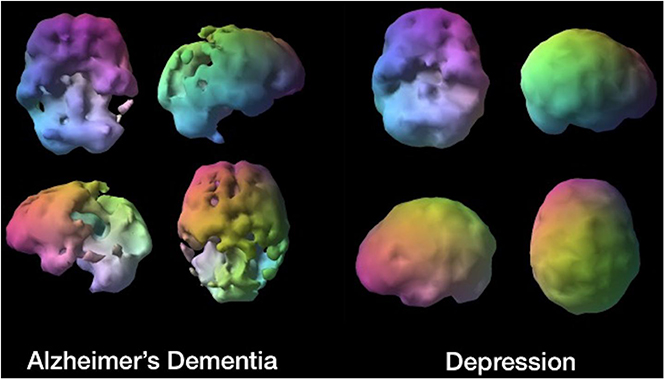

The potential of accelerator-reliant therapy and diagnostic techniques has increased considerably over the past decades, playing an increasingly important role in identifying and curing affections, such as cancer, that otherwise are difficult to treat; they also help to understand how major organs such as the brain function and thus to determine the underlying causes of diseases of growing societal significance such as dementia.